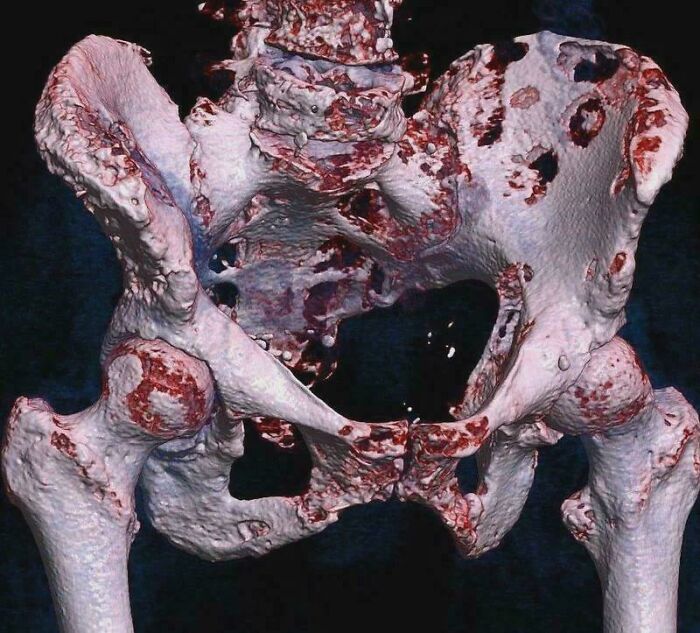

3D CT Scan of Hip Bone Cancer Spots

Look at those spots on the ilium! The vertebrae got hit too, causing a compression fracture. Medical imaging showing the not-so-pretty side of cancer.